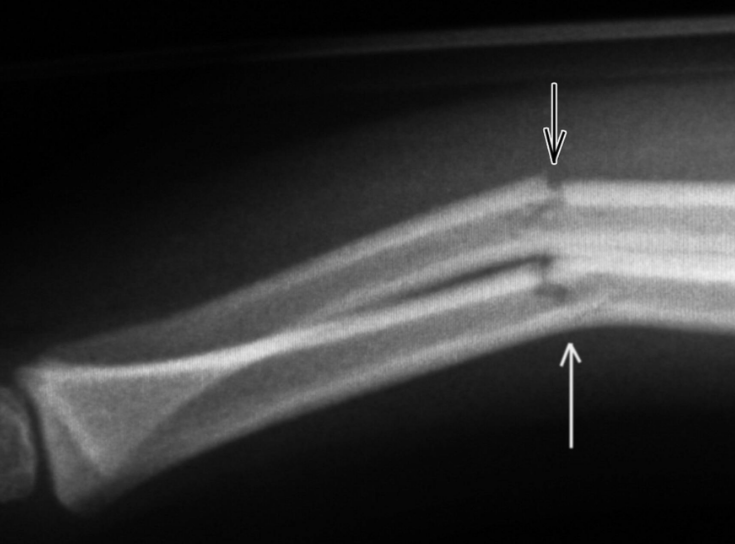

Question 2 : En se basant sur la classification de Salter pour les fractures chez les enfants, comment classifiez-vous la fracture sur l’image suivante ?

a) Fracture de type 1

b) Fracture de type 2

c) Fracture de type 3

d) Fracture de type 4

e) Fracture de type 5

A

d